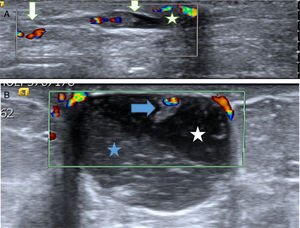

La mayor parte de los PB se diagnostican mediante ecografía2,3. Pueden presentar hallazgos ecográficos muy característicos (fig. 1A y B). En ocasiones son nódulos similares a los fibroadenomas y con menos frecuencia son lesiones sospechosas de malignidad (fig. 2 A)4,5.

A. Probable papiloma benigno (PB). Hallazgo ecográfico más frecuente y característico de PB. Paciente de 43 años con secreción uniorificial de mama izquierda. En la ecografía se apreció una lesión ecogénica con flujo doppler-color (flechas blancas) en el interior de un ducto dilatado (estructura tubular anecoica) que se correspondía con el ducto secretor, cercano al pezón (estrella). Hallazgo BIRADS 3. La BAV confirmó el diagnóstico de PB. B. Probable PB intraquístico. Hallazgo ecográfico poco frecuente pero característico de PB. Paciente de 53 años que acudió por nódulo palpable periareolar de mama derecha. La ecografía mostró una lesión quística con contenido espeso (estrella azul) sobre líquido menos espeso, anecoico (estrella blanca). En la pared superior del quiste se apreció un nódulo ecogénico con flujo doppler-color (sólido), característico de un PB intraquístico (flecha azul). Hallazgo BIRADS 3. La BAV confirmó el diagnóstico de PB.

En 87 lesiones no se realizó BAG previa y se consideraron probables PB (pPB) por los siguientes hallazgos ecográficos: 1) lesiones de aspecto probablemente benigno, asociadas o no a secreción uniorificial, en el interior de un ducto dilatado, con señal doppler-color o que se correspondían con defectos de repleción en la galactografía, y 2) lesiones de aspecto probablemente benigno en la pared de un quiste, con señal doppler-color (fig. 1 A y B). La secreción uniorificial se asociaba a 74 pPB. En la tabla 1 se recogen la clínica y la clasificación BIRADS de todas las lesiones.